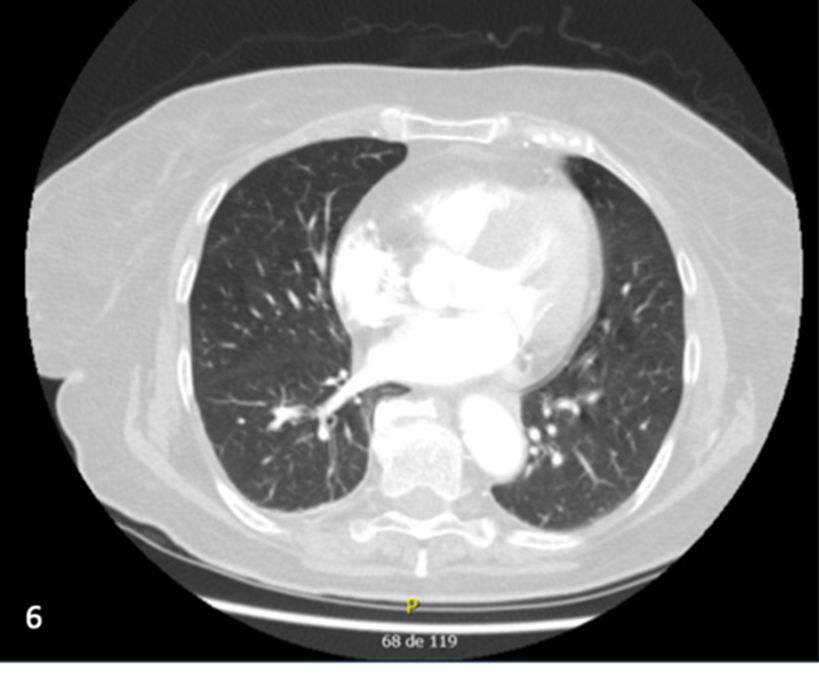

When Myeloma Extends Beyond the Bone Marrow: A Rare Pulmonary Manifestation

Rita Moreira, Sofia Rodrigues de Carvalho, Filipe da Cunha Pinto, Júlio Daniel Pacheco, Mariana Santos Freitas, Ana Areia Reis, Diana Pereira Anjos